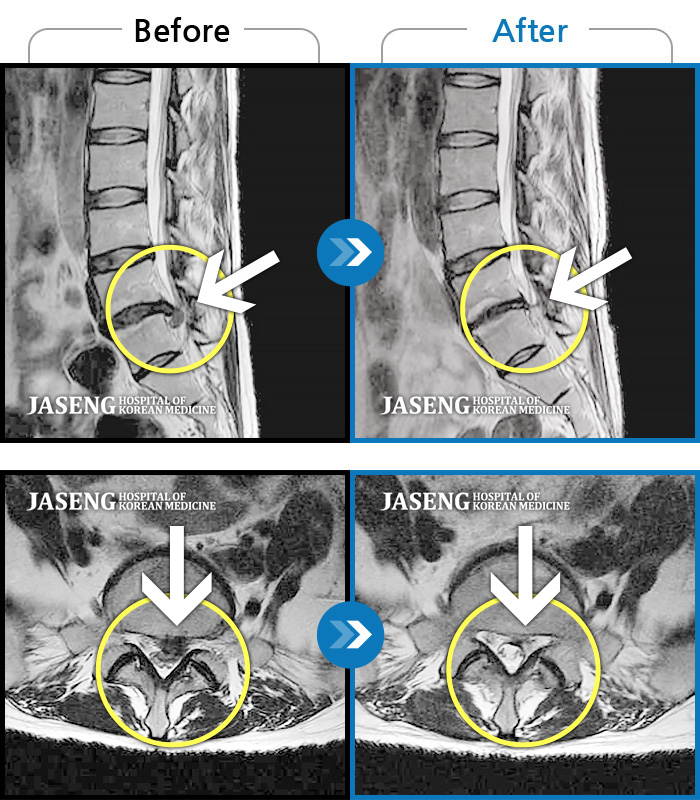

MRI 치료사례

허리,엉치 통증 있고 왼쪽 종아리, 발가락쪽으로 저림